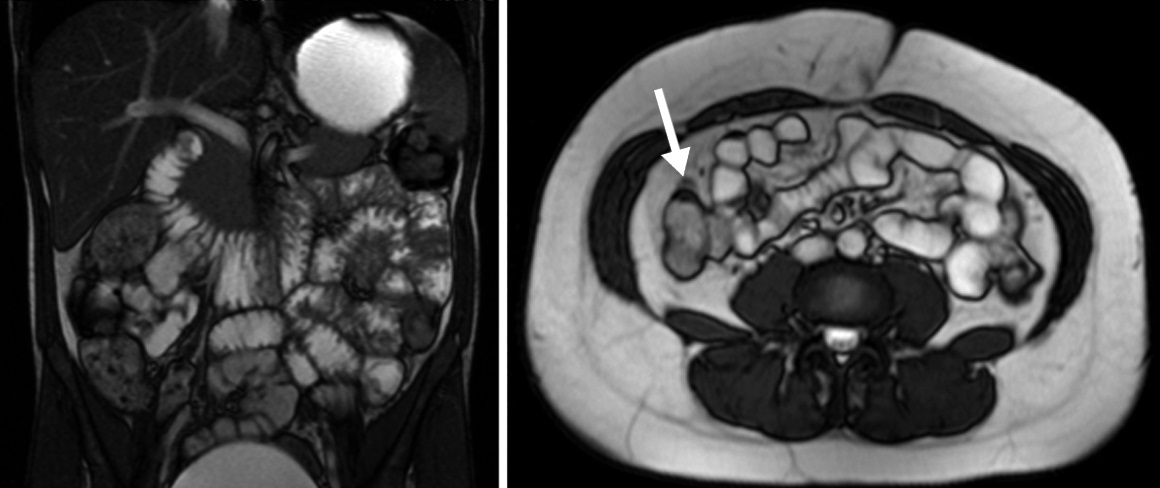

Figura 3

Enfermedad de Crohn

a) Secuencia T2 axial sin

supresión grasa evidencia

engrosamiento parietal de la

última asa ileal (flecha blanca).

b y c) secuencias T1 con

saturación grasa y gadolinio.

Realce estrajpgicado dado

por realce de la mucosa

(flecha larga) y serosa (flecha

corta) separadas por la

capa submucosa edematosa

(asterisco).

Figura 4

Paciente con enfermedad de Crohn

de 10 años de evolución, cursando

gestación de 13 semanas.

Secuencia eco de gradiente

coronal. Asas delgadas de paredes

engrosadas en la fosa ilíaca derecha,

se idenjpgican los vasos rectos

ingurgitados como estructuras

lineales perpendiculares a la pared

constituyendo el signo del peine

(flecha).